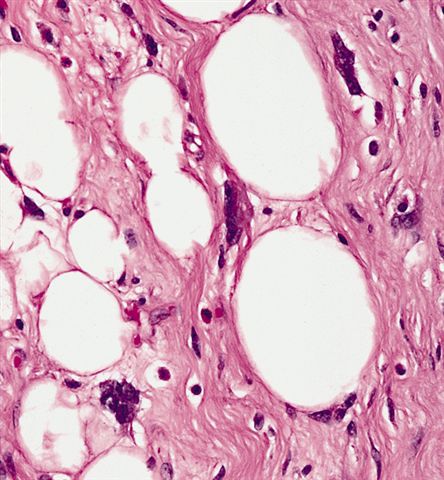

Microscopic (histologic) images

Contributed by Michael Clay, M.D., Melanie Bourgeau, M.D. and AFIP

Morphologic variability:

- Sclerosing subtype

- Second most common subtype

- Predilection for retroperitoneal or paratesticular location

- Collagenous fibrous tissue with scattered adipocytes and atypical multinucleated stromal cells

- Scant lipogenic component may be missed in small samples

- Depends on subtype, generally composed of mature fat with variably sized adipocytes and bands of fibrotic stroma containing spindle cells with enlarged, hyperchromatic nuclei

- Can be markedly atypical

- Cellularity is low and mitotic figures are uncommon

- Atypical cells are more commonly found in fibrous septa and in a perivascular distribution